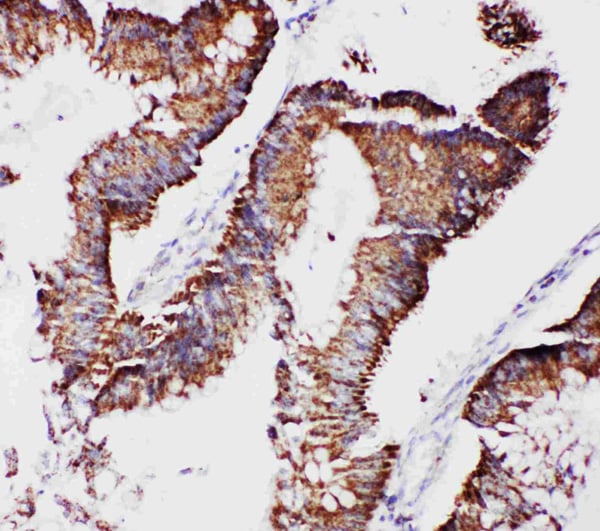

IHC (Immunohiostchemistry)

(Anti-mtTFA antibody, AAA45501, IHC(P)IHC(P): Human Intestinal Cancer Tissue)